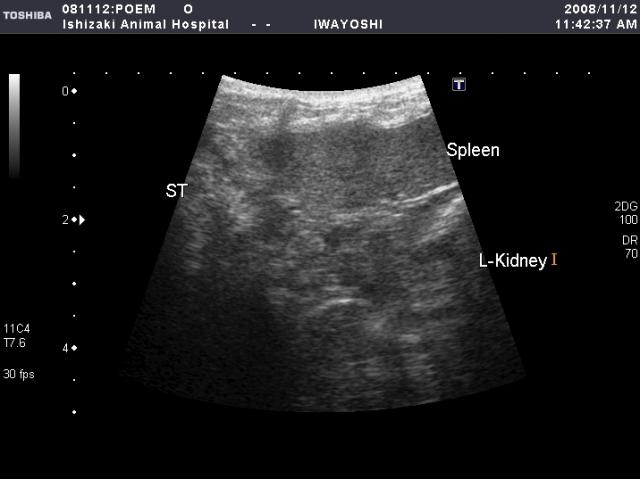

●脾臓

脾臓も、3つの部分(脾頭部、脾体部、脾尾部)に分けて検査します。

この像は、脾臓の頭の部分です。

脾体部・脾尾部を順に追っかけながら観察。

腎皮質(L-KID)と脾臓の組織の色を比較しそれぞれの異常の有無を観察します。